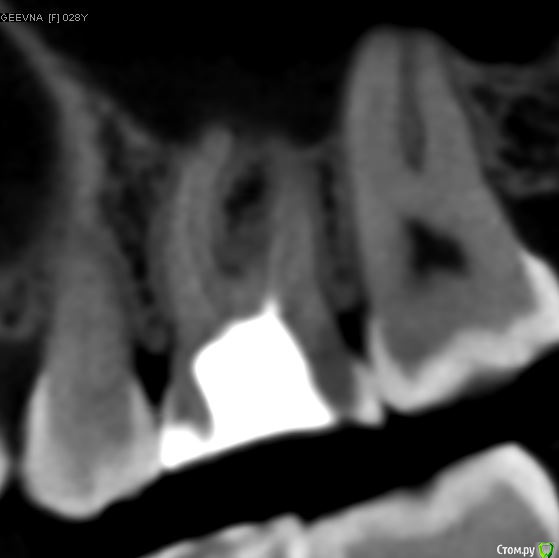

dmitrib81 Опубликовано 19 февраля, 2020 Поделиться Опубликовано 19 февраля, 2020 Помогите определить источник боли в зубе Ссылка на комментарий

krokomot Опубликовано 19 февраля, 2020 Поделиться Опубликовано 19 февраля, 2020 в медиальном корне недопломбировка и наличие вероятно 4ого канала. Ссылка на комментарий

dmitrib81 Опубликовано 20 февраля, 2020 Автор Поделиться Опубликовано 20 февраля, 2020 Зуб делали много лет назад. Примерно неделю назад появились периодические боли, бывает целый день не болит, потом снова ноющая боль. С приёмом пищи никак не связано. На горячие и холод реакции нетПодскажите, может ещё прислать фоток из КТ Пикассо, а то я в этом ничего не понимаю, просто разных фото экрана прислал, без какого-либо понимания, на что смотреть.. Ссылка на комментарий